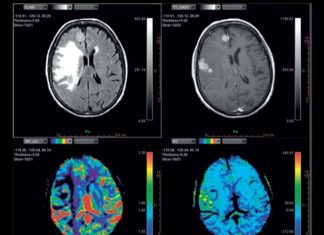

What is Medical Image Processing?

Medical image processing is a method that is used by the healthcare industry.

Using 3Dimage data sets, users can see very detailed images of the human body. Technology...